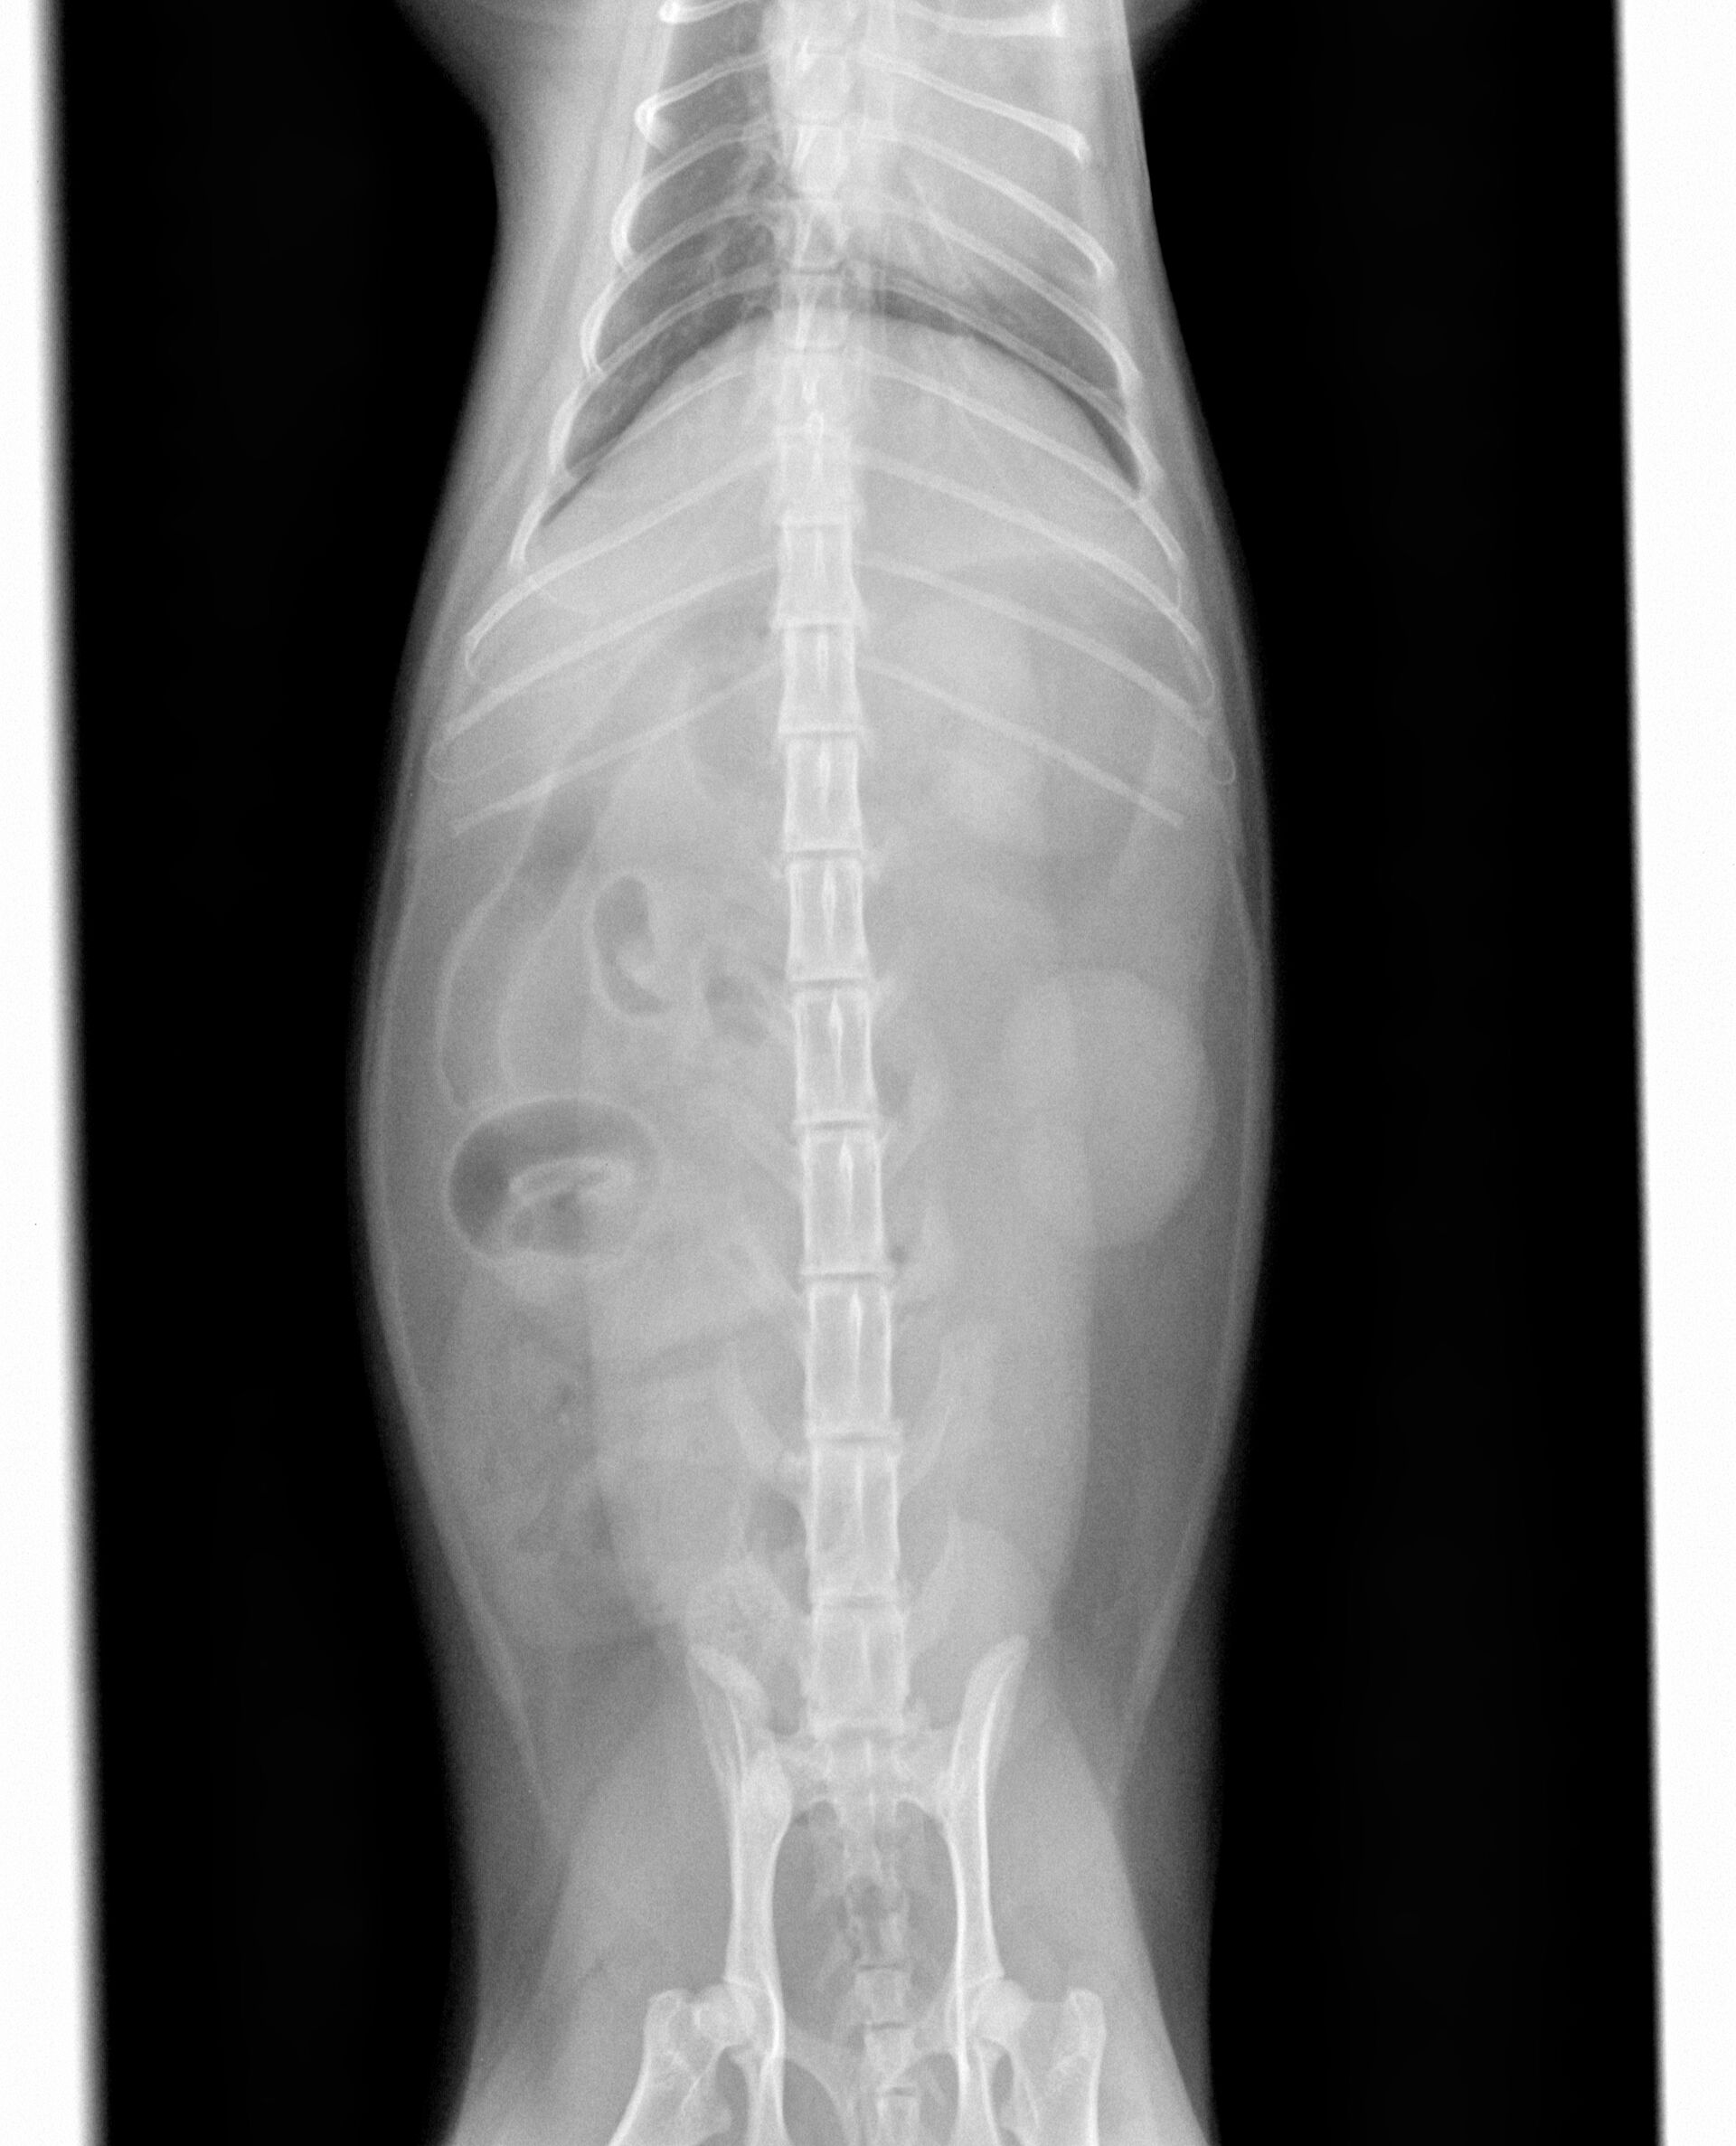

今回は、猫ちゃんの異物による腸閉塞です。症例の猫ちゃんは2歳の雄(去勢済)で、ある日食欲がなく、吐くということで来院されました。普段から紐や靴などを噛んで遊んでいるということだったので、レントゲンを撮りました。それが下の写真です。見た限りは特に異常は見当たりませんでした。